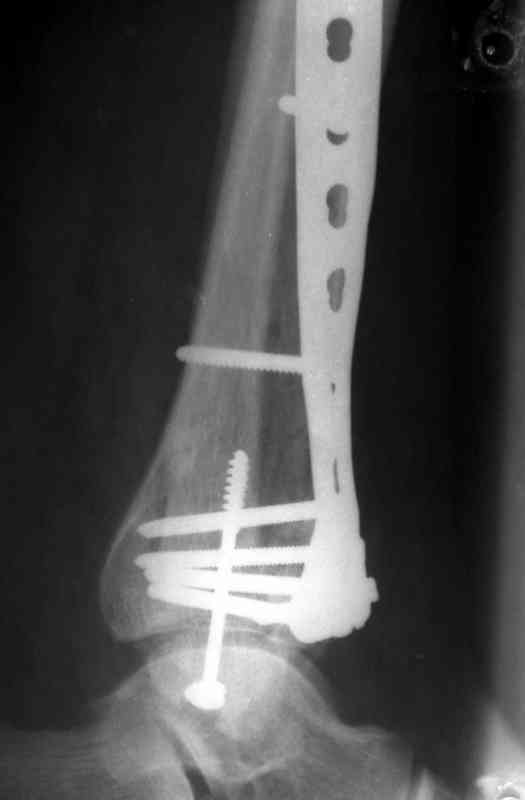

Посылаю результат лечения предыдущего больного через год.

С уважением Дрягин

Кстати, при переломах переднего края по классификации АО В-3 при переломах пилона пластина укладывается по передней поверхности. Она достаточно тонкая и эластичная, не надо этого бояться. Посылаю три снимка.